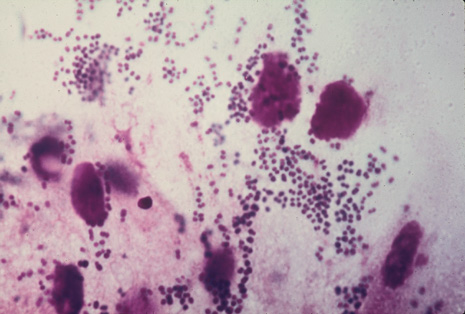

Many forms of uveitis are characterized by specific types of inflammatory cells. Usually, however, one encounters mixtures of cell types in any given specimen, with the relative percentages of lymphocytes and polymorphonuclear leukocytes varying. There may be unusual numbers of eosinophils, or macrophages laden with lens material may be present. Thus, an enumeration of the cells and a careful analysis of their structure can be useful as a diagnostic aid (Figs. 7, 8, 9, 10, 11, 12, 13, 14, 15, 16, 17, 18, 19, and 20). Figure 15 demonstrates eosinophils that were aspirated from the anterior chamber of a patient with Toxocara canis endophthalmitis. Figure 12 demonstrates malignant cell infiltrate from the vitreous, showing the stained presence of monoclonal light chains being elaborated in the cytoplasm. Interleukin-10, detectable in the vitreous of intraocular lymphoma patients, is also directly indicative of both the clinical activity and the number of malignant cells as observed by cytopathology.

Precise identification and culture of bacterial and fungal pathogens from both the aqueous humor and the vitreous fluid can be obtained. Gram's stain and Giemsa's stain smears of centrifuged specimens from the aqueous humor and the vitreous humor frequently demonstrate the bacterial or fungal causative agent. Attempts to isolate bacteria and fungi and to identify them on Gram's stain or Giemsa's stain smears have been most rewarding in the following cases: (a) postoperative endophthalmitis, (b) infection after a penetrating injury of the eye, (c) drug abuse patients with endogenous endophthalmitis (Figs. 21, 22, 23, 24, and 25), (d) patients receiving hyperalimentation, and (4) patients who are immunocompromised as a result of exogenous immunosuppressive agents.